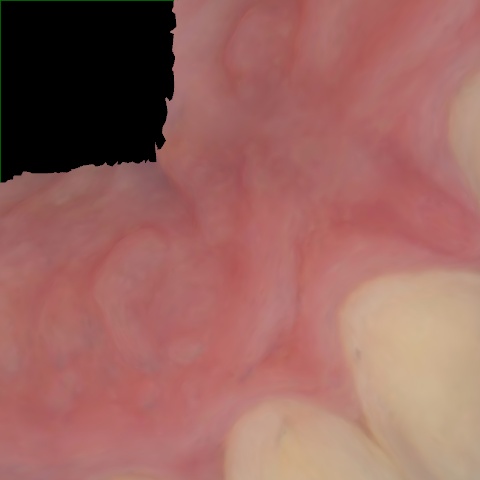

Annotated as "Good"